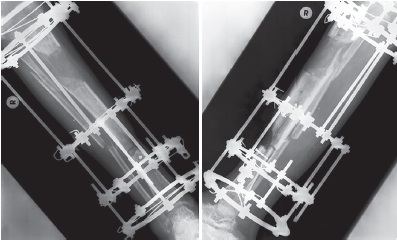

Через 14 мес. с момента ранения аппарат Илизарова был демонтирован (рис. 10). Анатомо-функциональный результат оценен через 18 мес. после ранения как хороший — 83 балла по шкале Neer – Grantham – Shelton [16]. Пациент ходит без дополнительных средств опоры, продолжает исполнять обязанности военной службы в соответствии с занимаемой должностью. Отсутствует тыльное сгибание правой стопы (рис. 10).

Рис. 10 (а). Рентгенограммы и внешний вид пациента через 18 мес. после ранения: а — рентгенограммы голени в прямой и боковой проекциях — можно видеть перестроившийся костный регенерат в верхней трети и сросшийся перелом в нижней трети большеберцовой кости, сросшийся перелом малоберцовой кости (b). Рентгенограммы и внешний вид пациента через 18 мес. после ранения: b — функциональный результат лечения

Figure 10 (а). X-rays and the appearance of the wounded 18 months after the injury: a — X-rays of the lower leg in frontal and lateral projections — a rebuilt bone regenerate in the upper third and a healed fracture in the lower third of the tibia, a healed fracture of the fibula are noted (b). X-rays and the appearance of the wounded 18 months after the injury: b — functional result of treatment